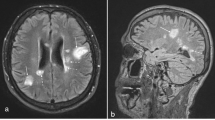

RA patients had contrast-enhanced cranial MRI scans on month 0 (before starting TNF blocker therapy and in the group receiving DMARD therapy). Both groups—the one started on TNF blocker therapy and the one continuing DMARD therapy—had follow-up cranial MRI scans at the end of the 6th month, which were assessed. The patients’ cranial MRI scans were evaluated by an experienced neurologist. The Fazekas scale was used to assess the white matter lesions that are indicators of small vessel disease and neurodegeneration. Based on this scale, the lesions detected in the periventricular white matter and deep white matter in T2-weighted or FLAIR sections were scored between 0 and 3. Fazekas scale on the basis of visual assessment both periventricular (0 = absent, 1 = caps or pencil lining, 2 = smooth halo, 3 = irregular periventricular hyperintensities extending into deep white matter) and subcortical areas (0 = absent, 1 = punctuate foci, 2 = beginning confluence of foci, 3 = large confluent areas). The total Fazekas score was calculated by adding the periventricular and subcortical scores [21, 22]. In the control group, cranial MR was pulled and evaluated using the same method.

The scoring of the cranial MRI lesions of both groups according to the Fazekas scale is given in Table 3. A hyperintense lesion was detected in the periventricular white matter of five patients, and the deep white matter of 19 patients out of the 58 patients found in the patient group. A hyperintense lesion was detected in the periventricular white matter of three patients, and the deep white matter of nine patients out of the 34 patients found in the control group. No statistically significant relationship was found between the patient group and the control group in terms of the number of hyperintense lesions observed in the white matter (p > 0.05). While a chronic lacuna was detected in 1 patient in each group, the presence of an acute lacuna was not detected.

The S100 beta, GFAP and Claudin levels of hyperintense lesions in the periventricular white matter and deep white matter of the brains of RA patients according to their Fazekas scores are shown in Table 5. No relationship was determined between the hyperintense lesions observed in the periventricular region in the cranial MRI and each of the three proteins. The S100 beta level was observed to significantly increase as the number of hyperintense lesions seen in the deep white matter increased (p < 0.05).

In this study, we found significantly elevated peripheral blood levels of the brain-specific proteins, S100β and GFAP, indicative of BBB dysfunction, in patients with RA relative to controls. In the RA group that was started on TNF blocker therapy, S100β and GFAP levels were significantly decreased 6 months after commencement of therapy compared with levels at the beginning of treatment. Cranial magnetic resonance imaging (MRI) findings did not differ between patients with RA and the control group. In patients with RA, S100β levels increased with the number of lesions in the deep white matter observed on cranial MRI.

MRI provides different benefits using different techniques for the assessment of neurological involvement. Morphological changes in the brain can be assessed in T1-weighted sections, and the microstructural form of the tissue can be assessed in T2-weighted sections. T2-weighted images can be used to identify hyperintense lesions associated with inflammatory and degenerative changes in the white matter, hyperintense lesions that increase with age in normal populations, and hyperintense lesions associated with microvascular disease [39].

Hamed et al. [14] reported hyperintense lesions and small or lacunar ischemic lesions in the deep white matter, periventricular, and gray–white matter junction areas on MR-FLAIR sections in some patients with RA and no neurological deficit. In another quantitative T2-weighted MRI study, no difference was detected between the RA and control groups in terms of white matter lesions [40]. In the present study, hyperintense lesions were detected in the periventricular region in five of 58 patients with RA and in the deep white matter of 19 patients, and a chronic lacunar infarct was detected in one patient. Consistent with other studies, we found no significant difference between the RA and control groups in terms of white matter lesions in the present study. Similar to the study of Hamed et al. [14] we also found that S100β levels increased with the number of hyperintense lesions in the deep white matter observed on cranial MRI in patients with RA.